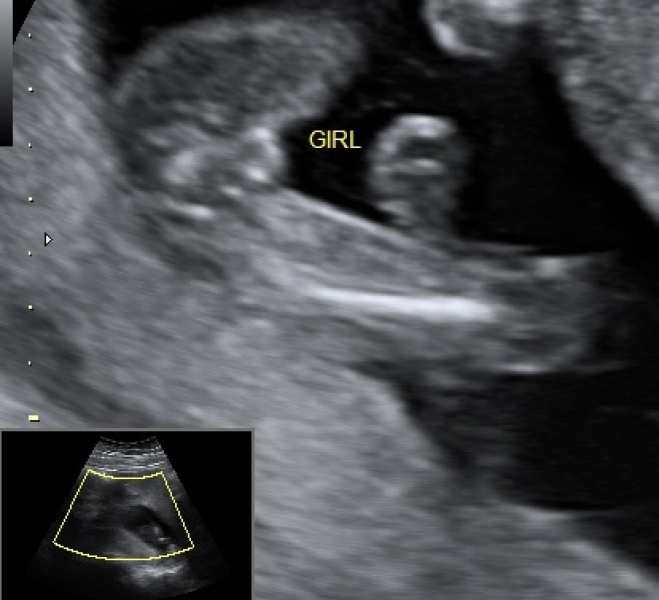

I’m a new mum stressing about the gender of our baby - it was our 16 weeks & 3 days scan would you say it’s defiantly a girl or would you say it’s wrong please help

I'd say girl. My boy at 16 weeks was very obvious!

Looks like a girl to me but I'm no expert!